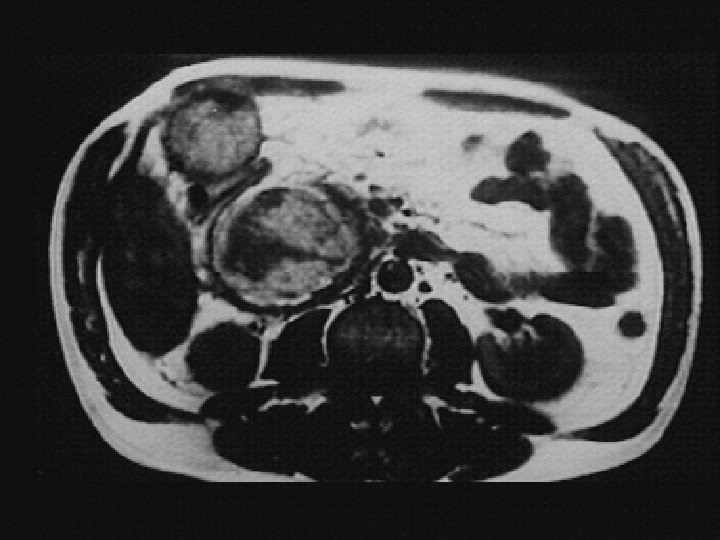

Apparition d’un pseudo -kyste du pancréas

Pseudo-kyste de la tête

PK tête PK queue PK Queue PK corps